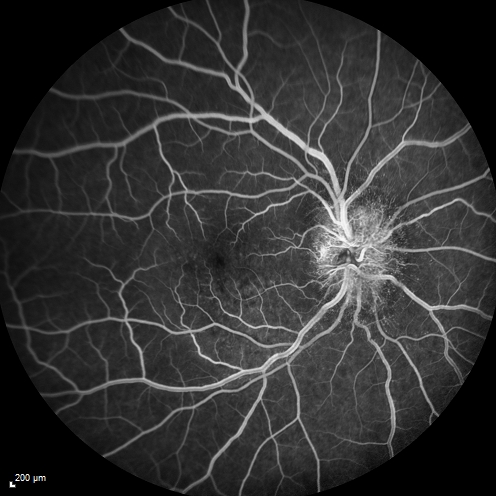

Syphillitic Optic Neuropathy and Maculopathy

46 year old woman with 2 weeks of vision loss OD.  VA 20/200 OD; 20/20 OS.  there are posterior vitreous cells on OCT in both eyes.  ICG, FAF, and FA show an abnormal macula OD.  VA improved to 20/30 within a month with treatment with PCN.